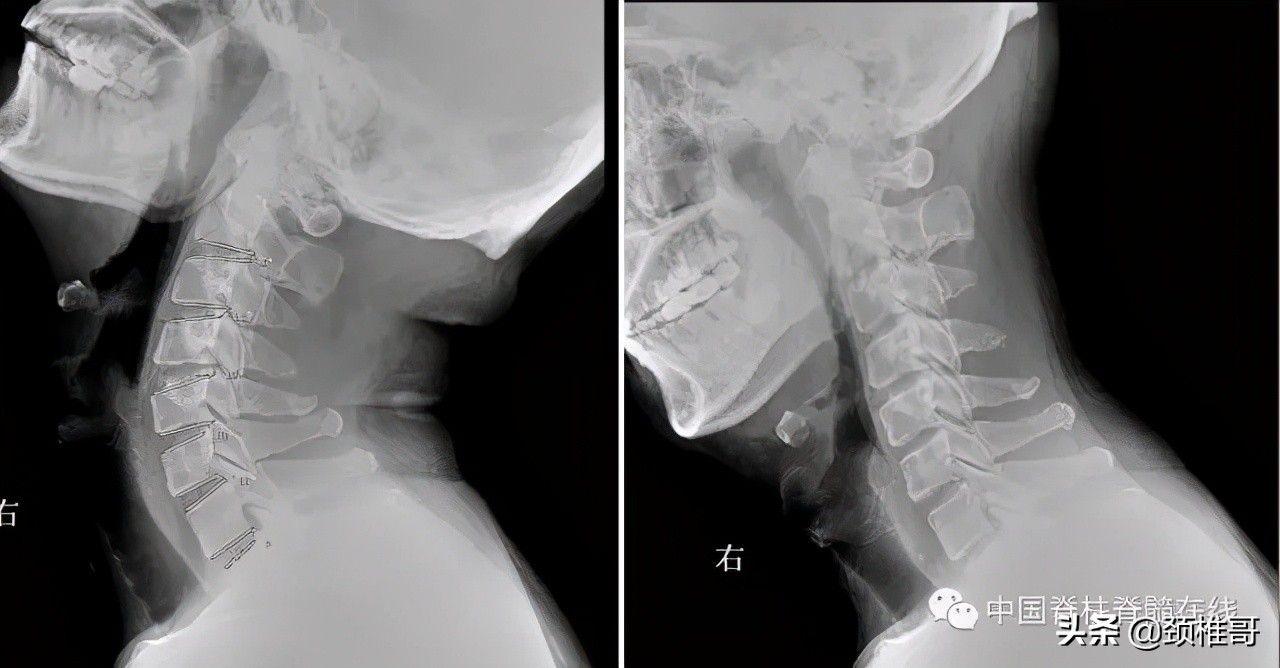

另外一个例子,这是一个头晕8年的病人,他的颈椎核磁共振显示,颈椎3-6各个节段之间的椎间盘退变膨出,局部有一些骨质增生,但没有明显的神经受压,横断面扫描显示颈椎周围肌肉有严重的退变表现;在X线检查时发现,棘突排列顺序不佳,颈4/5椎体之间有台阶,颈椎3-7各个节段之间夹角增大,都超过了11度;过屈位显示颈2-4椎出现了双边征,是旋转不稳的表现。这个病人的椎间盘虽然已经出现了退变、膨出,并发生了骨质增生,对硬膜囊产生了轻度压迫。但是其主要问题是椎间盘退变吗?不对,其主要问题还是多节段的椎间不稳,既有夹角增大,又有台阶,还有旋转。导致此病人头晕的主要原因还是肌肉和韧带的控制能力的下降所导致的。

正位显示椎体序列不佳、侧位显示颈椎4/5之间台阶状改变

过伸过屈侧位X线片显示多节段颈椎不稳

在椎间盘膨出、颈椎不稳基础上发生的代偿性增生